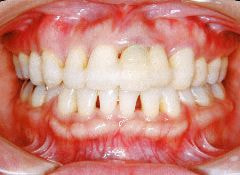

治療例1 (インプラント補綴+矯正)